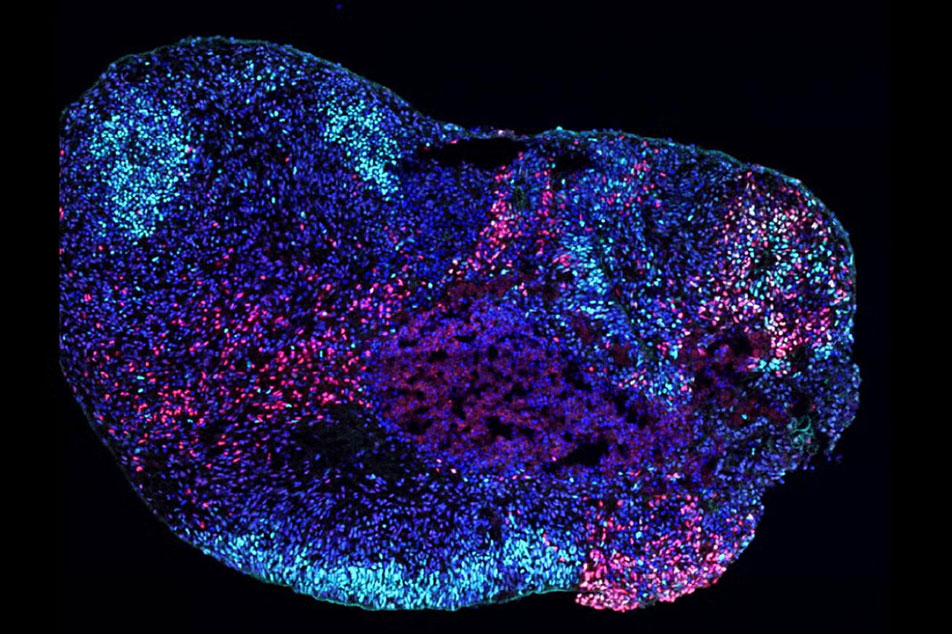

Unlocking the brain’s secrets: How epilepsy genes affect different regions

Thanks to a study using advanced 3D brain models, scientists at UCLA Broad Stem Cell Research Center discovered that a single gene variant can cause a variety of developmental problems often seen alongside epilepsy. These stem cell-derived models could become a vital tool for developing treatments for epilepsy and other cognitive and behavioral challenges.

UCLA reproductive scientist Amander Clark is advancing infertility treatments by studying how stem cells develop into egg and sperm precursors, aiming to create functional reproductive cells in the lab.

-